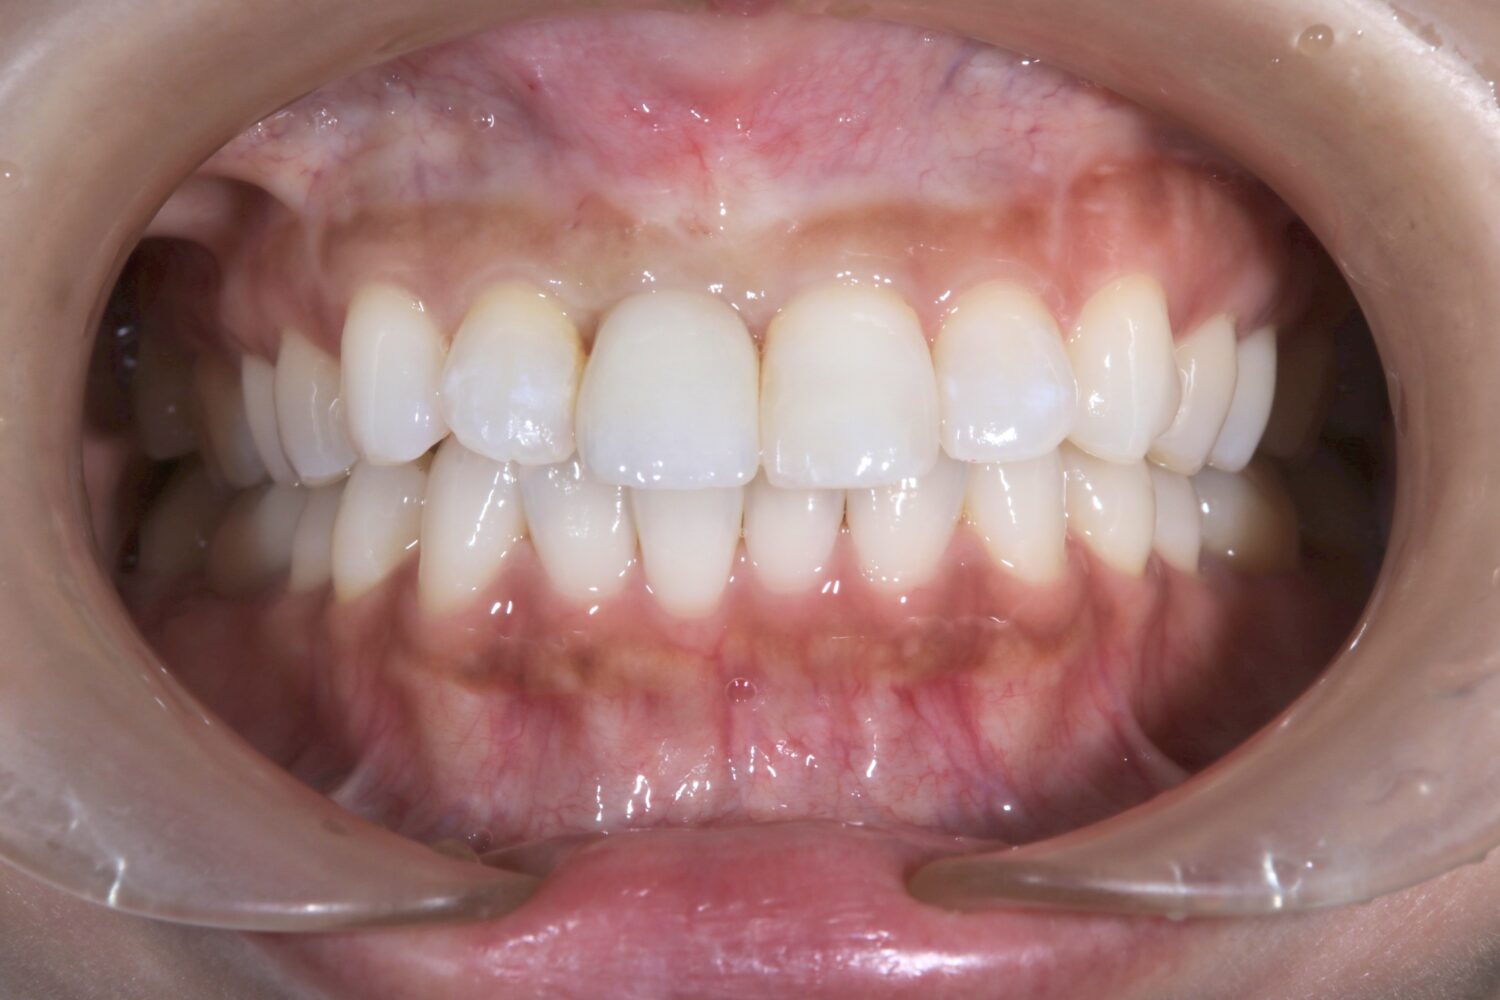

最終補綴物の装着|自然な見た目と噛み心地を回復

治療期間中は仮歯を装着し、歯の形・色・歯ぐきとの調和・噛み合わせを確認しながら調整しました。

最終的に、インプラント上にセラミッククラウンを装着し、前歯としての見た目と機能の回復を図りました。

術前後の比較